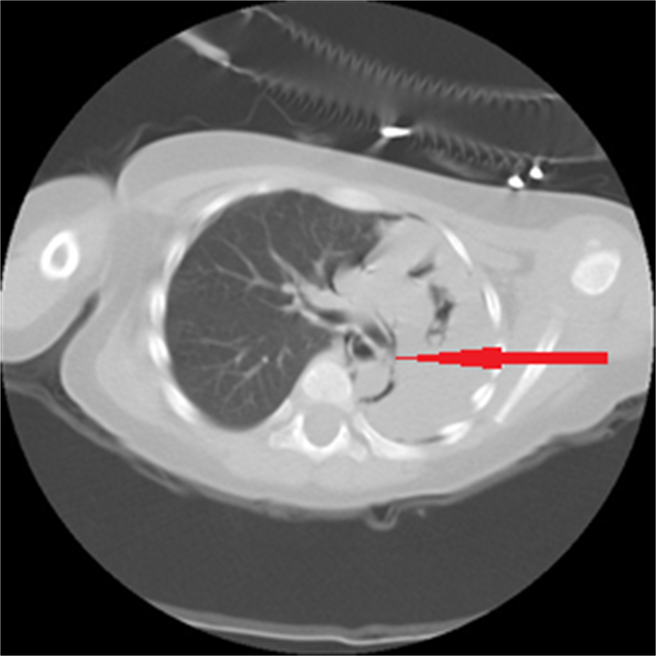

这名男童被家属紧急送往当地医院急诊室血氧浓度只有70%,先紧急插管处罝,胸部X光检查结果为左肺全塌陷合併严重纵膈腔漏气及皮下气肿,胸部电脑断层检查结果为主气管与左支气管交接处有异物,经胸部电脑断层检查结果为气管有异物,因而再转诊到中国医药大学儿童医院。